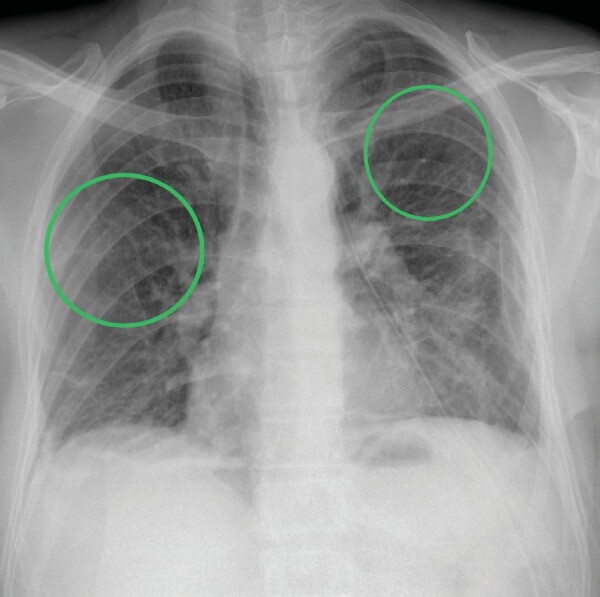

Birt-Hogg-Dubé syndrome: A case series highlighting pulmonary manifestations, rare renal involvement and role of familial diagnosis.